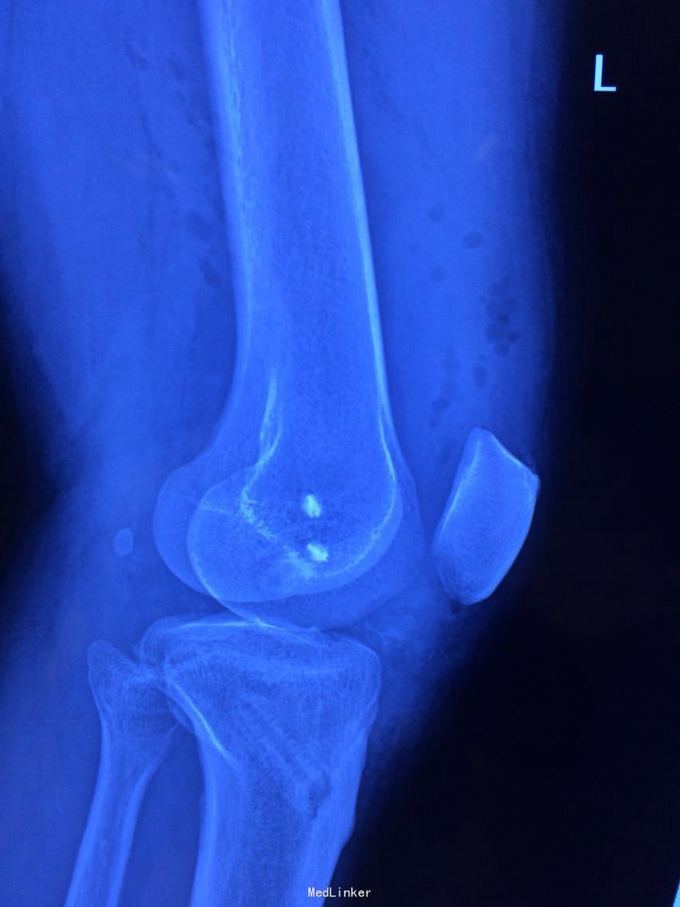

交通伤后膝关节疼痛,关节不稳。 患者交通伤,膝关节肿胀、疼痛,活动受限,肿胀消退后关节不稳。

查体:髌骨稳定,拉赫曼试验阴性,台阶征阳性3+,拨号征阴性,外翻0度阴性、30度阳性,内翻阴性。

诊断:膝关节多发韧带损伤,后交叉韧带、内侧副韧带 处理:给予关节镜下后交叉韧带重建,小切口修补内侧副韧带,取自体半腱股薄肌腱